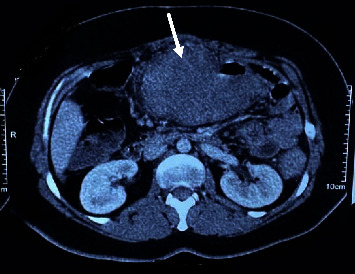

Introduction: Basidiobolomycosis is a rare fungal infection caused by an environmental saprophyte, Basidiobolus ranarum. It usually presents as a chronic subcutaneous infection; however, few cases of gastrointestinal involvement have been reported. The exact transmission route of gastrointestinal cases is not clear, and diagnosis always requires a high index of suspicion because it tends to mimic other inflammatory and neoplastic conditions. Case Report. A 31-year-old immunocompetent woman presented with abdominal pain and an advanced colon mass. She was completely well until about 1.5 years ago, when she underwent bariatric surgery. One year after surgery, chronic abdominal pain developed. A colonoscopy showed an ulcerative lesion in the descending colon, and the biopsy was in favor of ulcerative colitis. Despite immunosuppressive treatment, there was no improvement, and with worsening symptoms, more investigations revealed advanced colon mass with entrapment of the stomach and pancreas. Colonic mucosa biopsy and trucut biopsy of the mass showed just necrosis and acute inflammation; thus, she underwent exploratory laparotomy with colectomy, partial gastrectomy, distal pancreatectomy, and left nephrectomy. On pathologic examination, there was granulomatous inflammation plus the Splendore-Hoeppli phenomenon around fungal hyphae, which was diagnostic for gastrointestinal basidiobolomycosis. Previous pathology slides were reviewed and revealed a tiny focus of basidiobolomycosis. After 6 months of treatment with itraconazole, she is relatively well without any clinical or radiologic abnormalities.

Conclusion: Our case highlights the significance of suspicion for basidiobolomycosis in ulcerative and necrotic lesions with increased eosinophils, especially in the presence of abdominal mass and systemic eosinophilia.